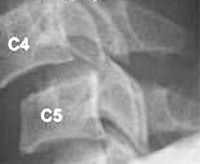

- Рентгенография крестца. Применяется в большинстве случаев, считается самым доступным способом исследования. С помощью рентгеновского снимка можно увидеть направление смещения крестца.

Для уточнения локализации, характера и выраженности смещения выполняют рентгенографию позвоночника с использованием стандартных и дополнительных проекций. При подозрении на патологические изменения дисков (протрузию диска, межпозвоночную грыжу) назначают МРТ позвоночника. При наличии неврологических нарушений пациента направляют на консультацию к неврологу. Для оценки функционального состояния периферических нервов используют электромиографию. При подозрении на нарушения кровоснабжения головного мозга проводят реоэнцефалографию.

Определяющим моментом в диагностике повреждений крестца является рентгенография в двух проекциях. Однако более чем в половине случаев с подозрением на перелом крестца требуется дополнительное рентгенологическое обследование. Эти сведения дают томограммы во фронтальной и сагиттальной проекциях, рентгенограммы в косых проекциях, а также рентгенограммы в прямой проекции при наклоне трубки кзади на 40-50°. В особо сложных случаях диагноз устанавливают с помощью КТ. Учитывая преимущественно множественный характер повреждений крестца, прямая проекция должна включать все кости таза, IV и V поясничные позвонки, а боковая — нижнепоясничные позвонки, копчик.